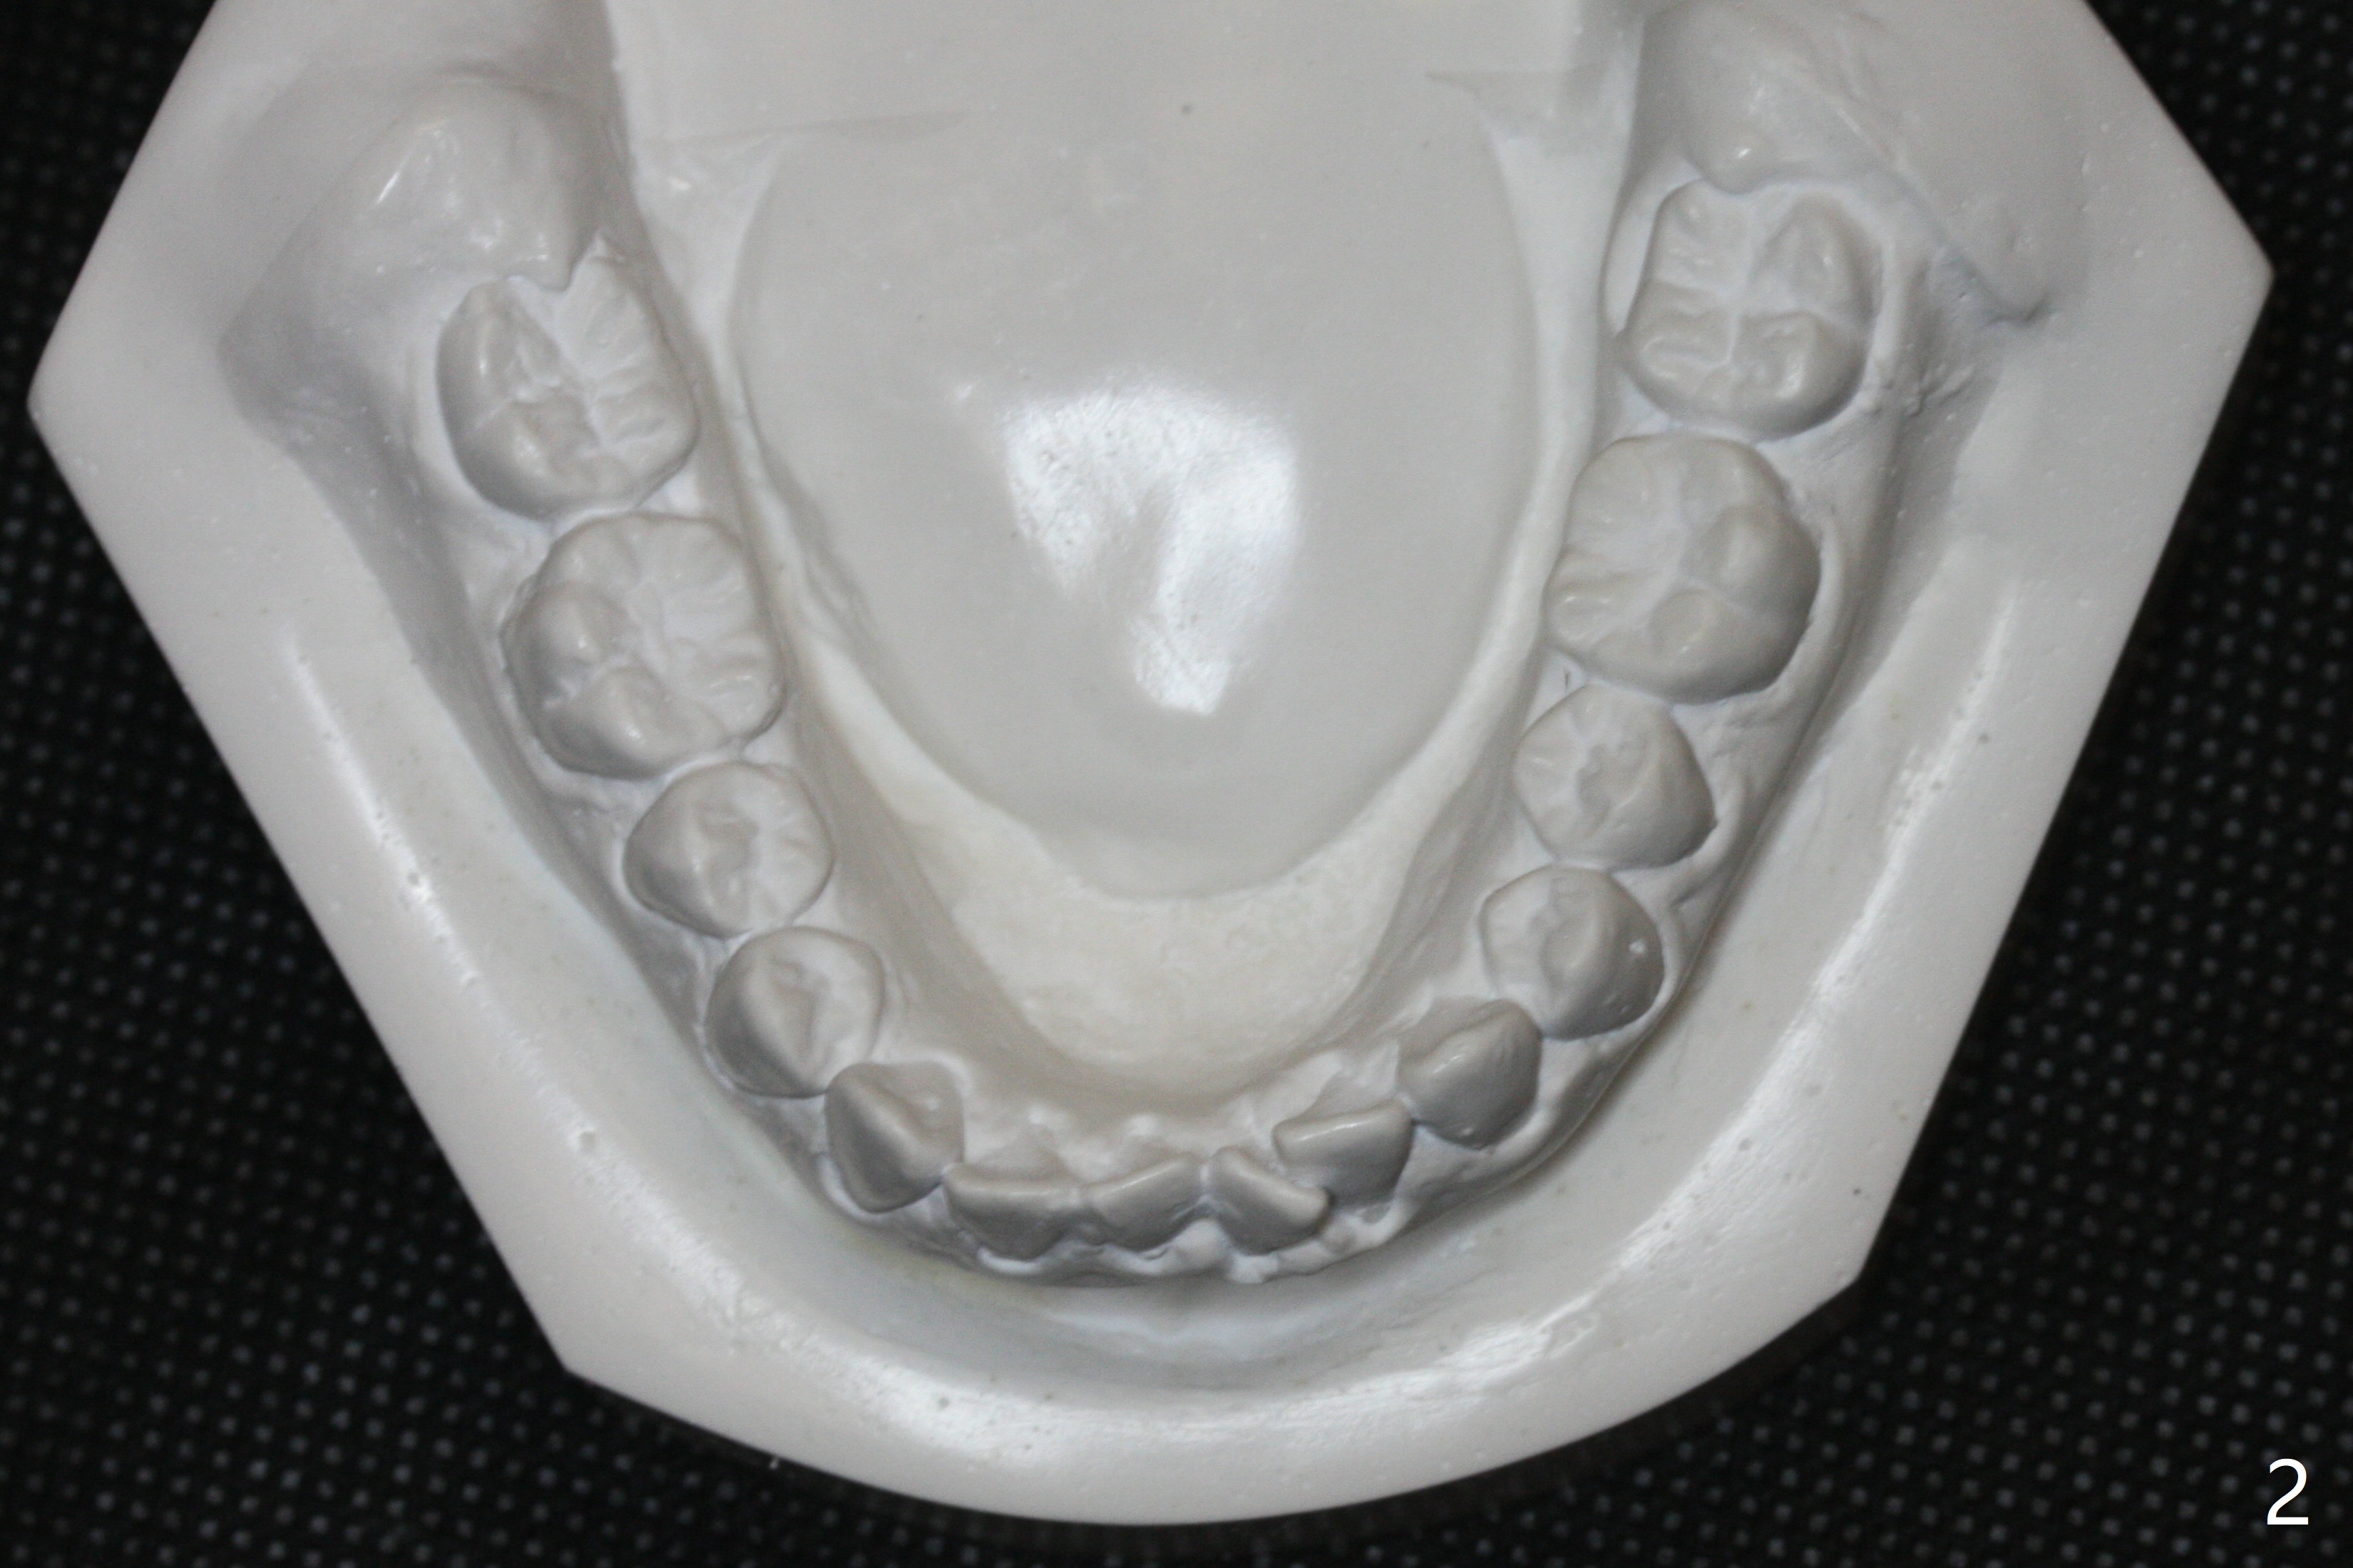

Since the lower anterior crowding is severe for a 15-year-old girl (Fig.2), lingual retainer is chosen for the lower arch (Fig.4), while a suck down one for the upper (Fig.1,3). No composite is applied to LR2 because the retainer wire adapts to the tooth nicely (Fig.4). In fact Dr. Shaughnessy does not apply composite to LL2 as well.